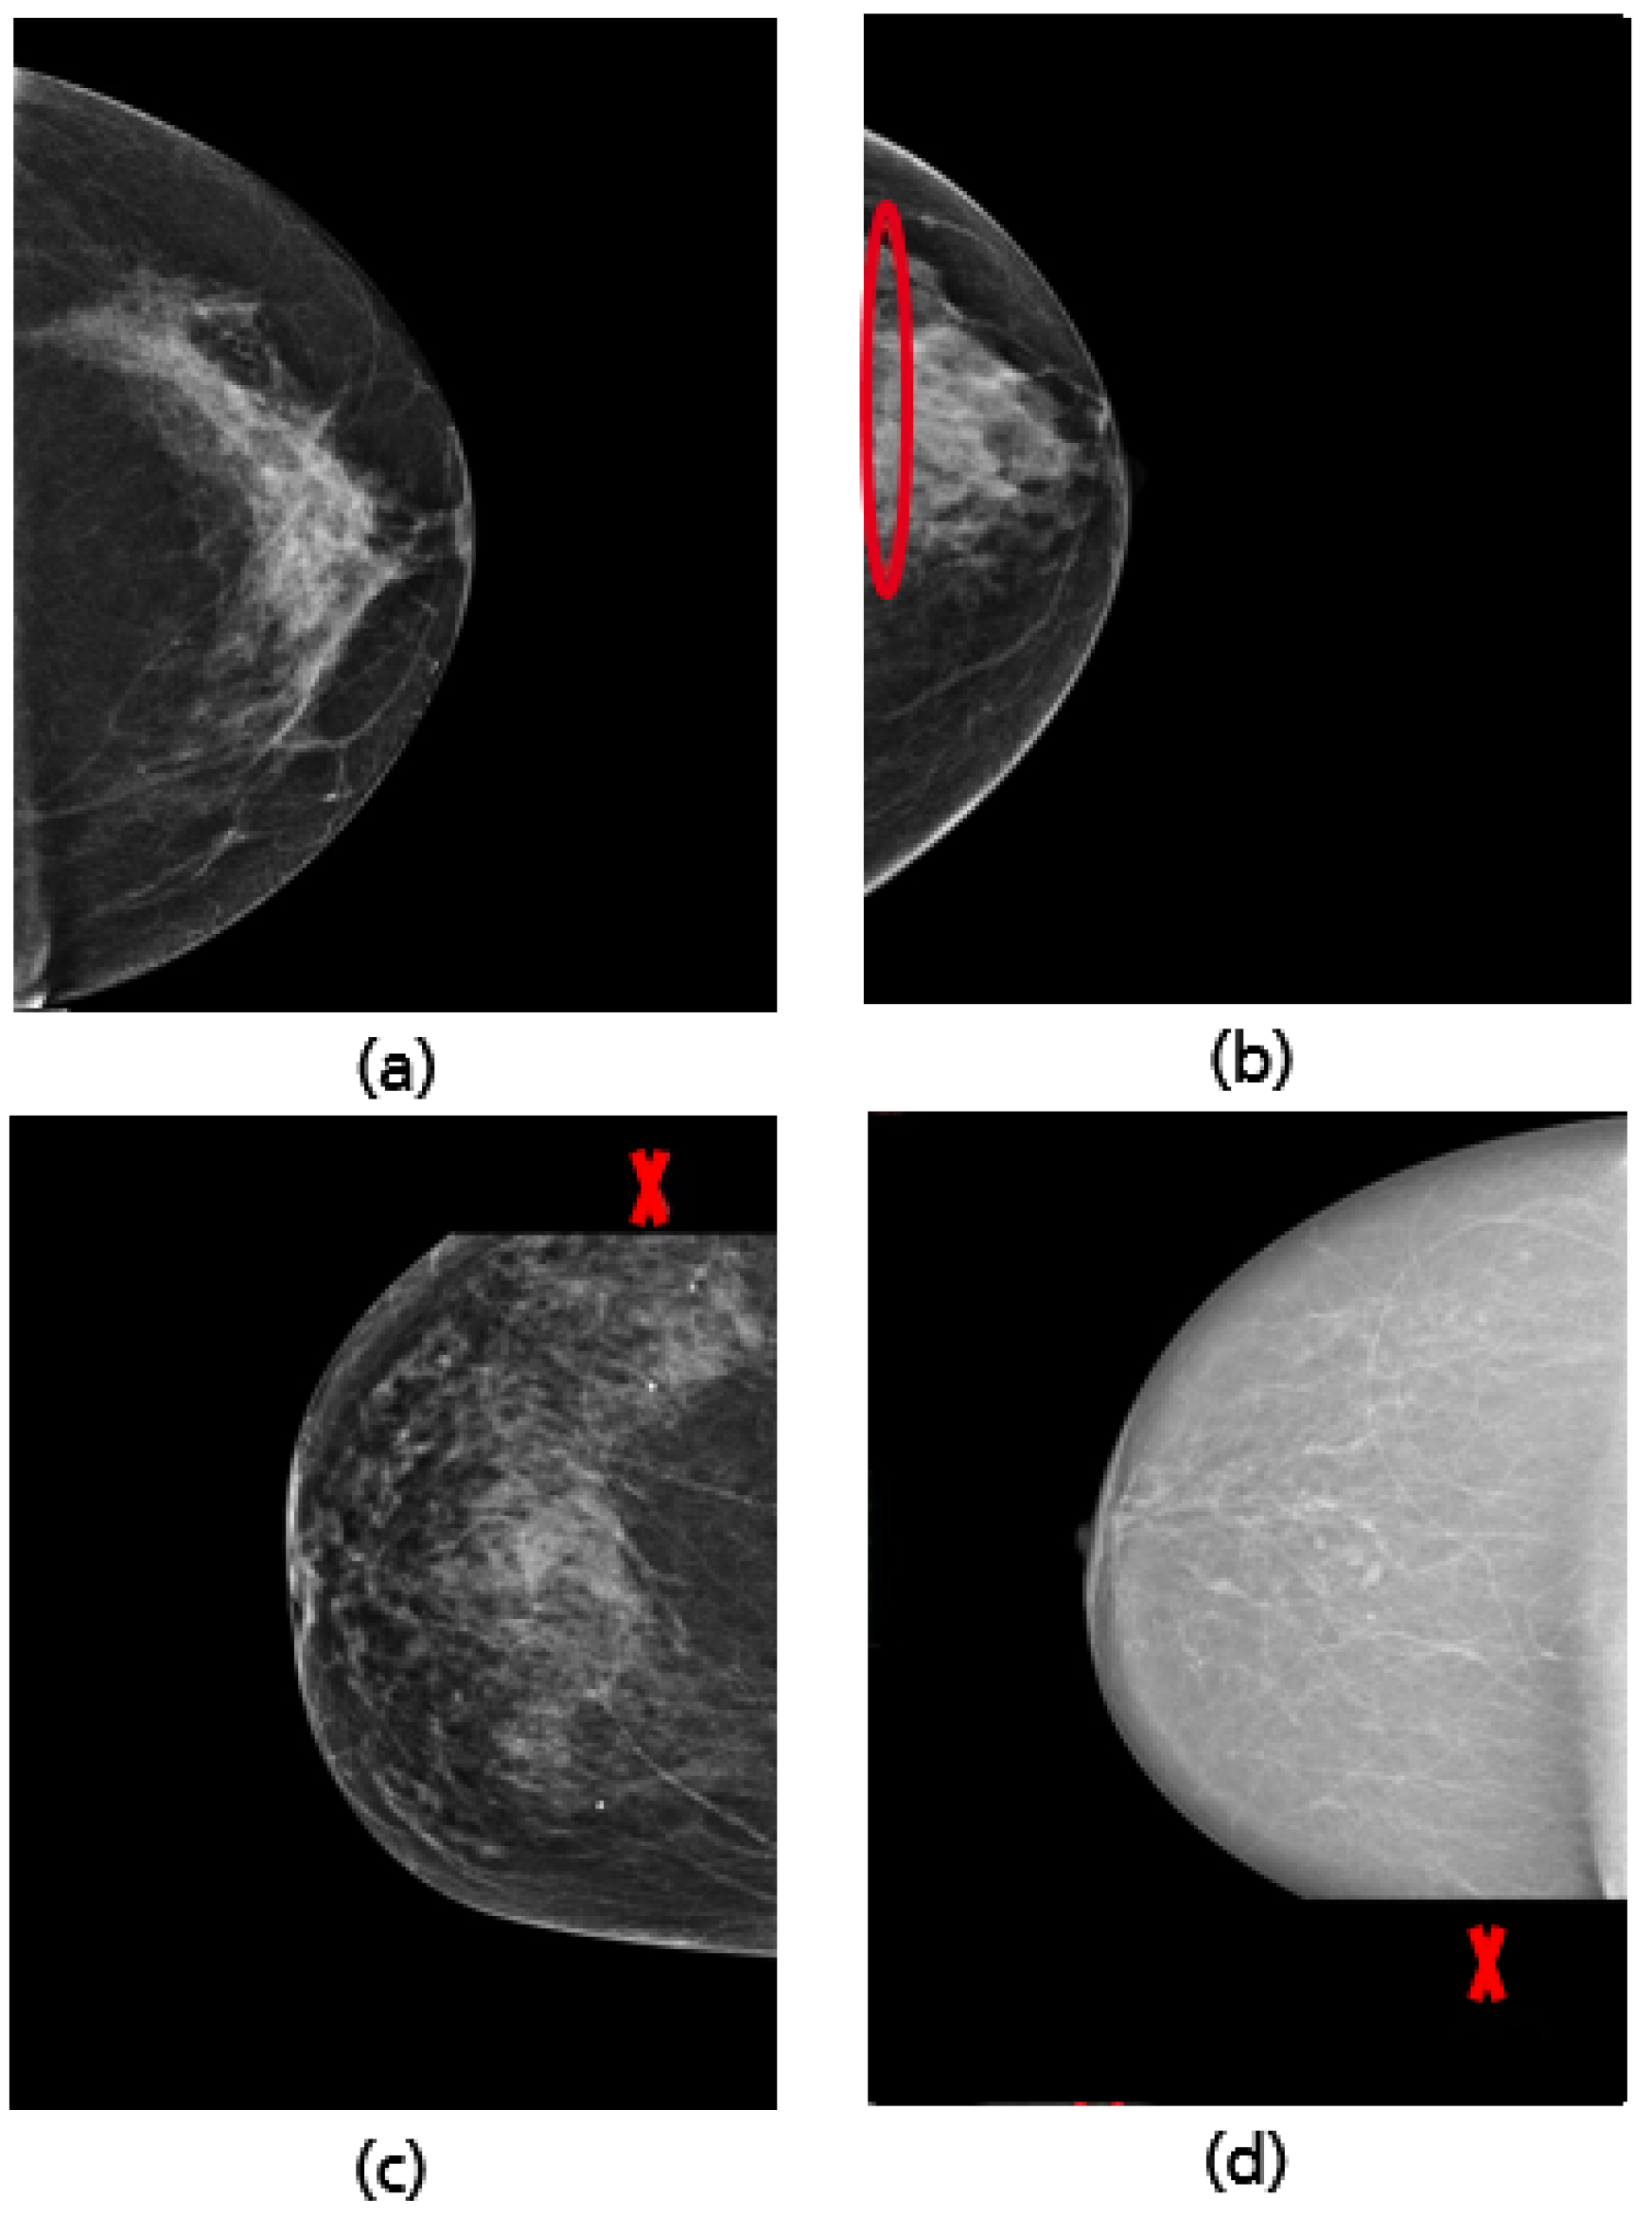

2.1. Mediolateral-Oblique View

2.2. Cranio-Caudal View